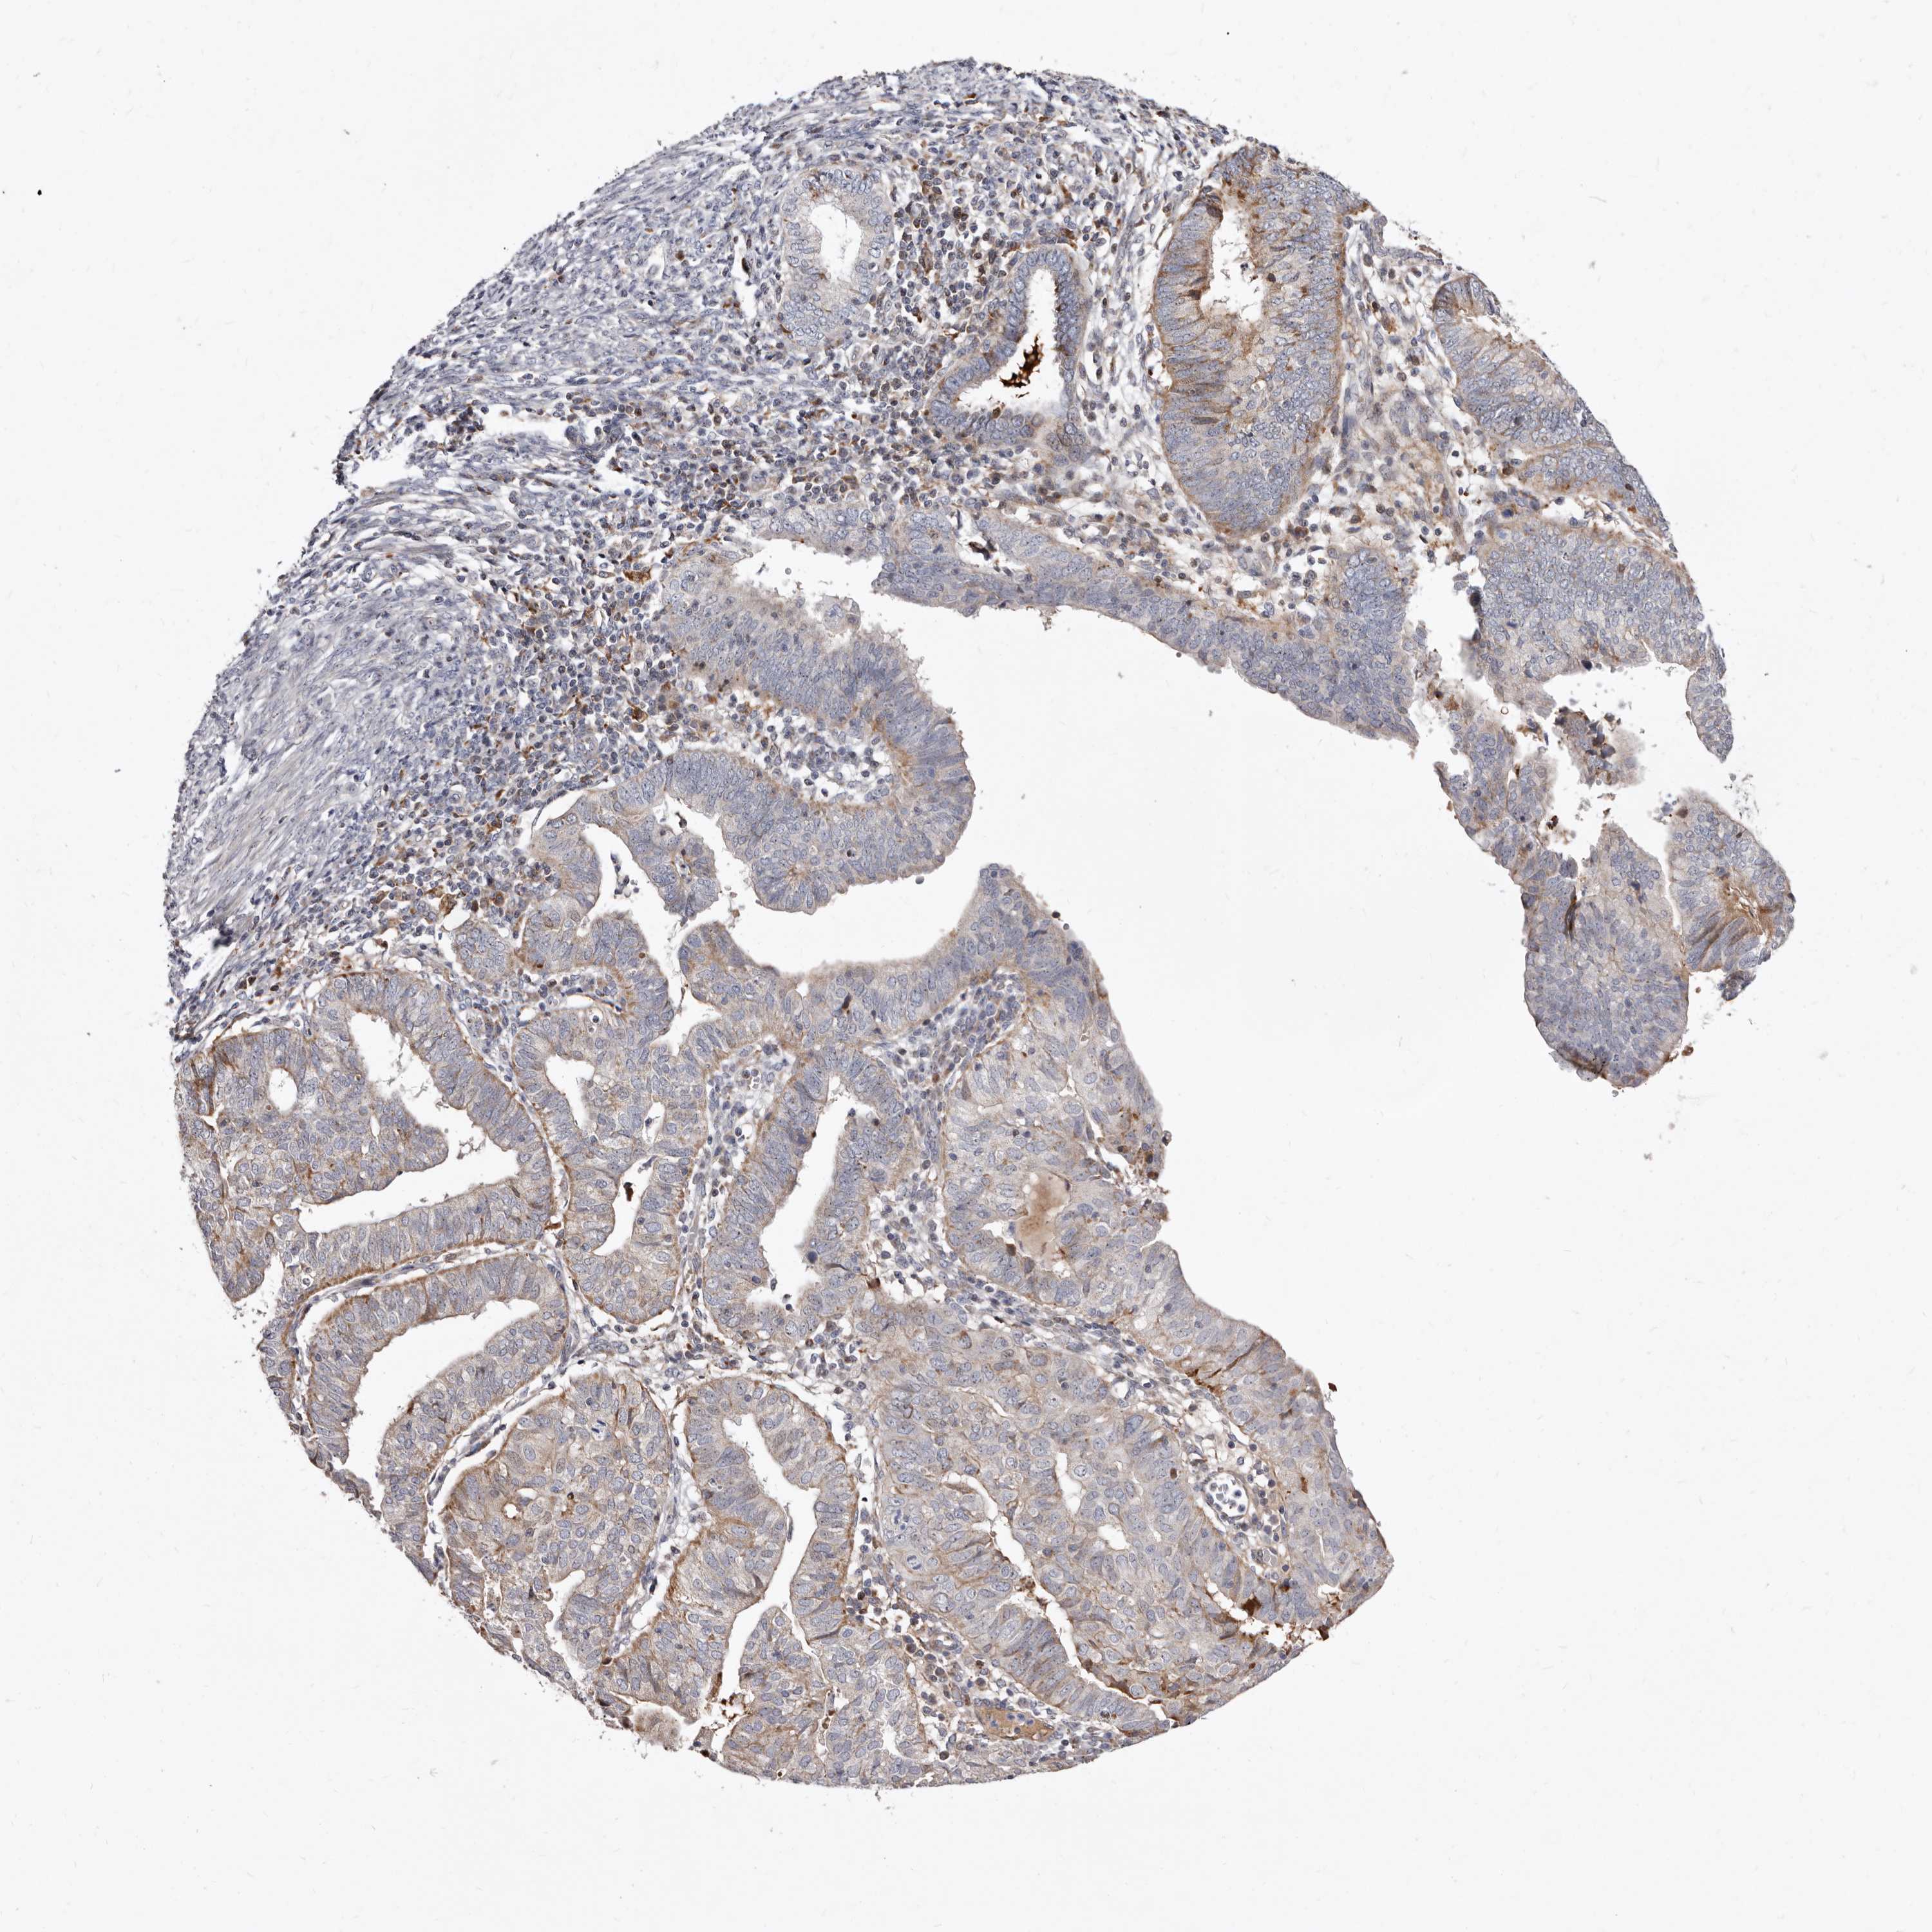

ENDOMETRIAL CANCER - Protein expressioni

A mouse-over function shows sample information and annotation data. Click on an image to view it in a full screen mode. Samples can be filtered based on level of antibody staining by selecting one or several of the following categories: high, medium, low and not detected. The assay and annotation is described here.

Note that samples used for immunohistochemistry by the Human Protein Atlas do not correspond to samples in the TCGA dataset.

Antibody stainingi

Antibody staining in the annotated cell types in the current human tissue is reported as not detected, low, medium, or high, based on conventional immunohistochemistry profiling in selected tissues. This score is based on the combination of the staining intensity and fraction of stained cells.

Each image is clickable and will lead to virtual microscopy that enables deeper exploration of all samples and also displays staining intensity scores, fraction scores and subcellular localization as well as patient and tissue information for each sample.

Antibody HPA029203

Staining

High

Medium

Low

Not detected

Intensity

Strong

Moderate

Weak

Negative

Quantity

>75%

75%-25%

<25%

None

Location

Nuclear

Cytoplasmic/membranous

Cytoplasmic/membranous,nuclear

Adenocarcinoma, NOS

Adenocarcinoma, metastatic, NOS